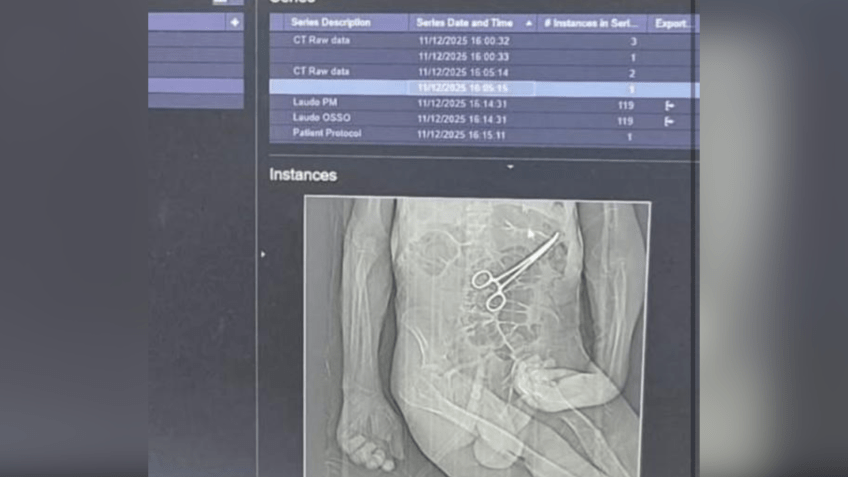

O filho conta que só ficou sabendo que uma pinça havia sido esquecida dentro do corpo de seu pai, após uma rádio local ter acesso ao raio X e veicular a notícia de que o objeto havia sido deixado após a primeira cirurgia. Veja a imagem da pinça:

Pinça teria sido esqeucida após primeria cirurgia • Reprodução